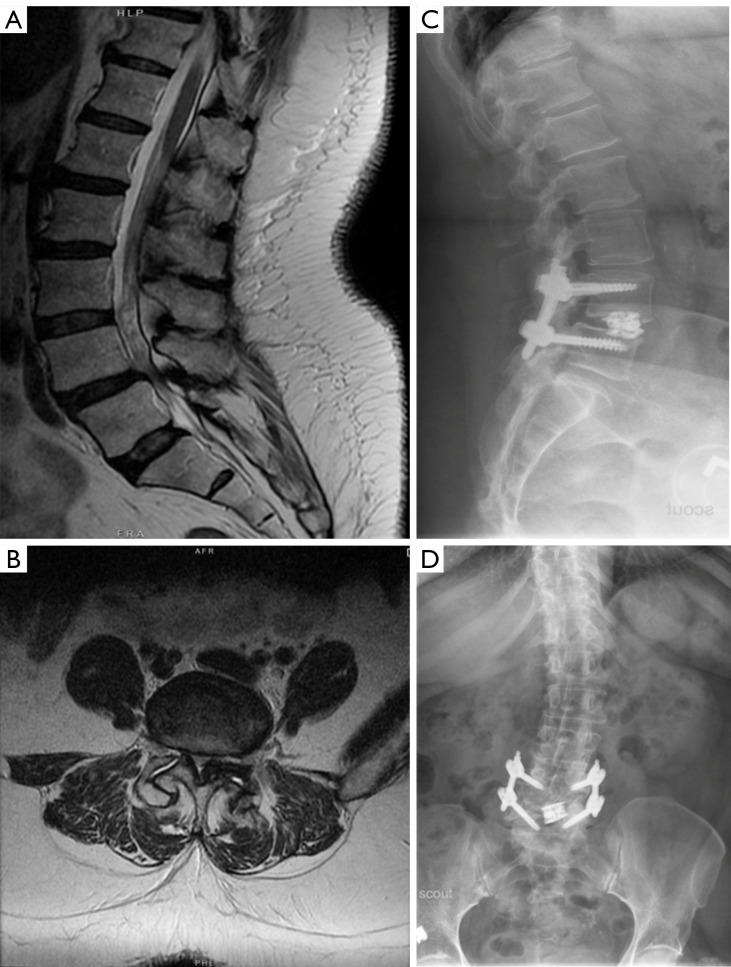

Abstract Image